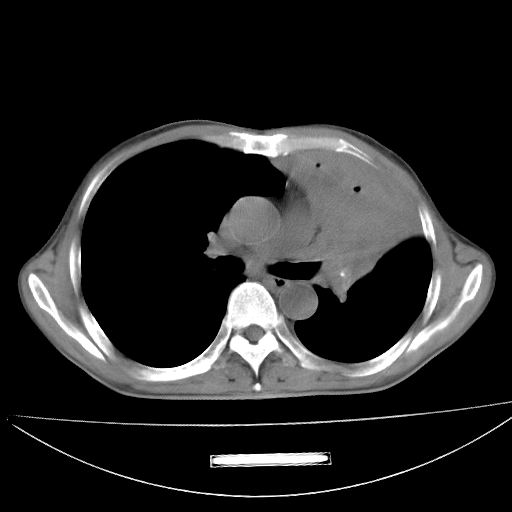

以下是引用杀毒软件在2009-4-28 17:58:00的发言:[br]考虑----左肺慢性肺脓肿形成继发上叶含气不良---抗炎后复查---待排肿瘤所致[br][br][本贴已被 杀毒软件 于 2009-4-28 18:01:26 修改过]